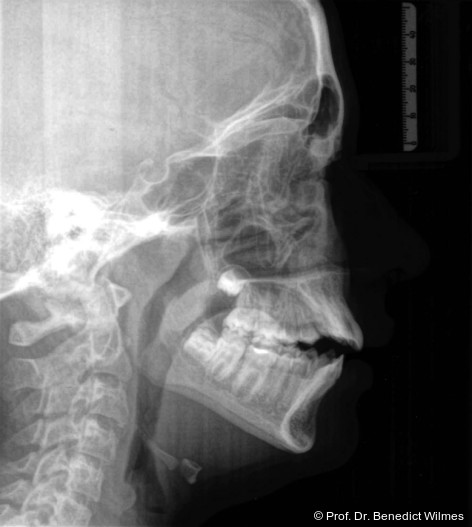

Eine 13-jährige Patientin stellte sich mit beidseitigem Kreuzbiss, einem anterioren offenen Biss und einer Angle Klasse II vor. Das viszerale Schluckmuster wurde mittels logopädischer Maßnahmen umgestellt, der offene Biss persistierte jedoch (Abb. 3a–l).

3. Autorotation der Mandibula zur Korrektur des anterior offenen Bisses, zudem auch zur Korrektur der Klasse II-Relation.

Als alternative Therapie wurde die chirurgische Korrektur des offenen Bisses nach Abschluss des Wachstums vorgeschlagen. Eltern und Patientin entschieden sich allerdings für die non­chirurgische und weniger invasive Molarenintrusion.